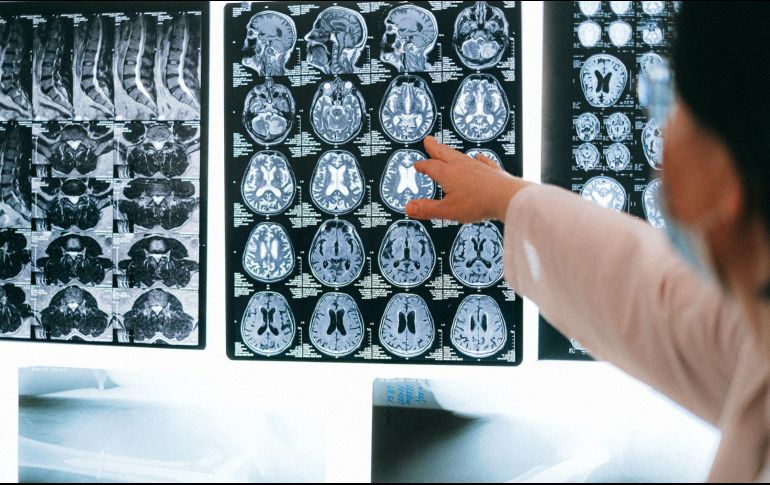

Investigadores proponen un nuevo modelo computacional relacionado con el Alzheimer. ESPECIAL/CORTESÍA MAYO CLINIC.

Los investigadores de Mayo Clinic propusieron un nuevo modelo para hacer un mapa de los síntomas de la enfermedad de Alzheimer en la anatomía cerebral. El modelo se creó mediante la aplicación de aprendizaje automático a los datos de imágenes cerebrales de los pacientes. Abarca todo el funcionamiento del cerebro, en lugar de regiones o redes cerebrales específicas, para explicar la relación entre la anatomía cerebral y el procesamiento mental.